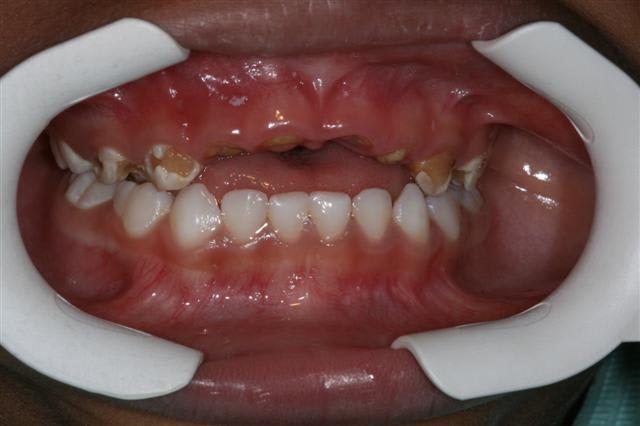

traitement global: ns aussi,en pedo,on peut!

à court terme,d'accord mais c'est mieux que rien(des dents de lait:les soigner? pourquoi faire?)

antoine: bientôt 5 ans

fin

pr les anterieures sup on verra en rentrant,radios à l'appui,et en fonction de la rhizalyse si ça vaut le coup de les remplacer

pr le moment:

Debut 1 akftnu - Eugenol

Fin 1 yocx2b - Eugenol